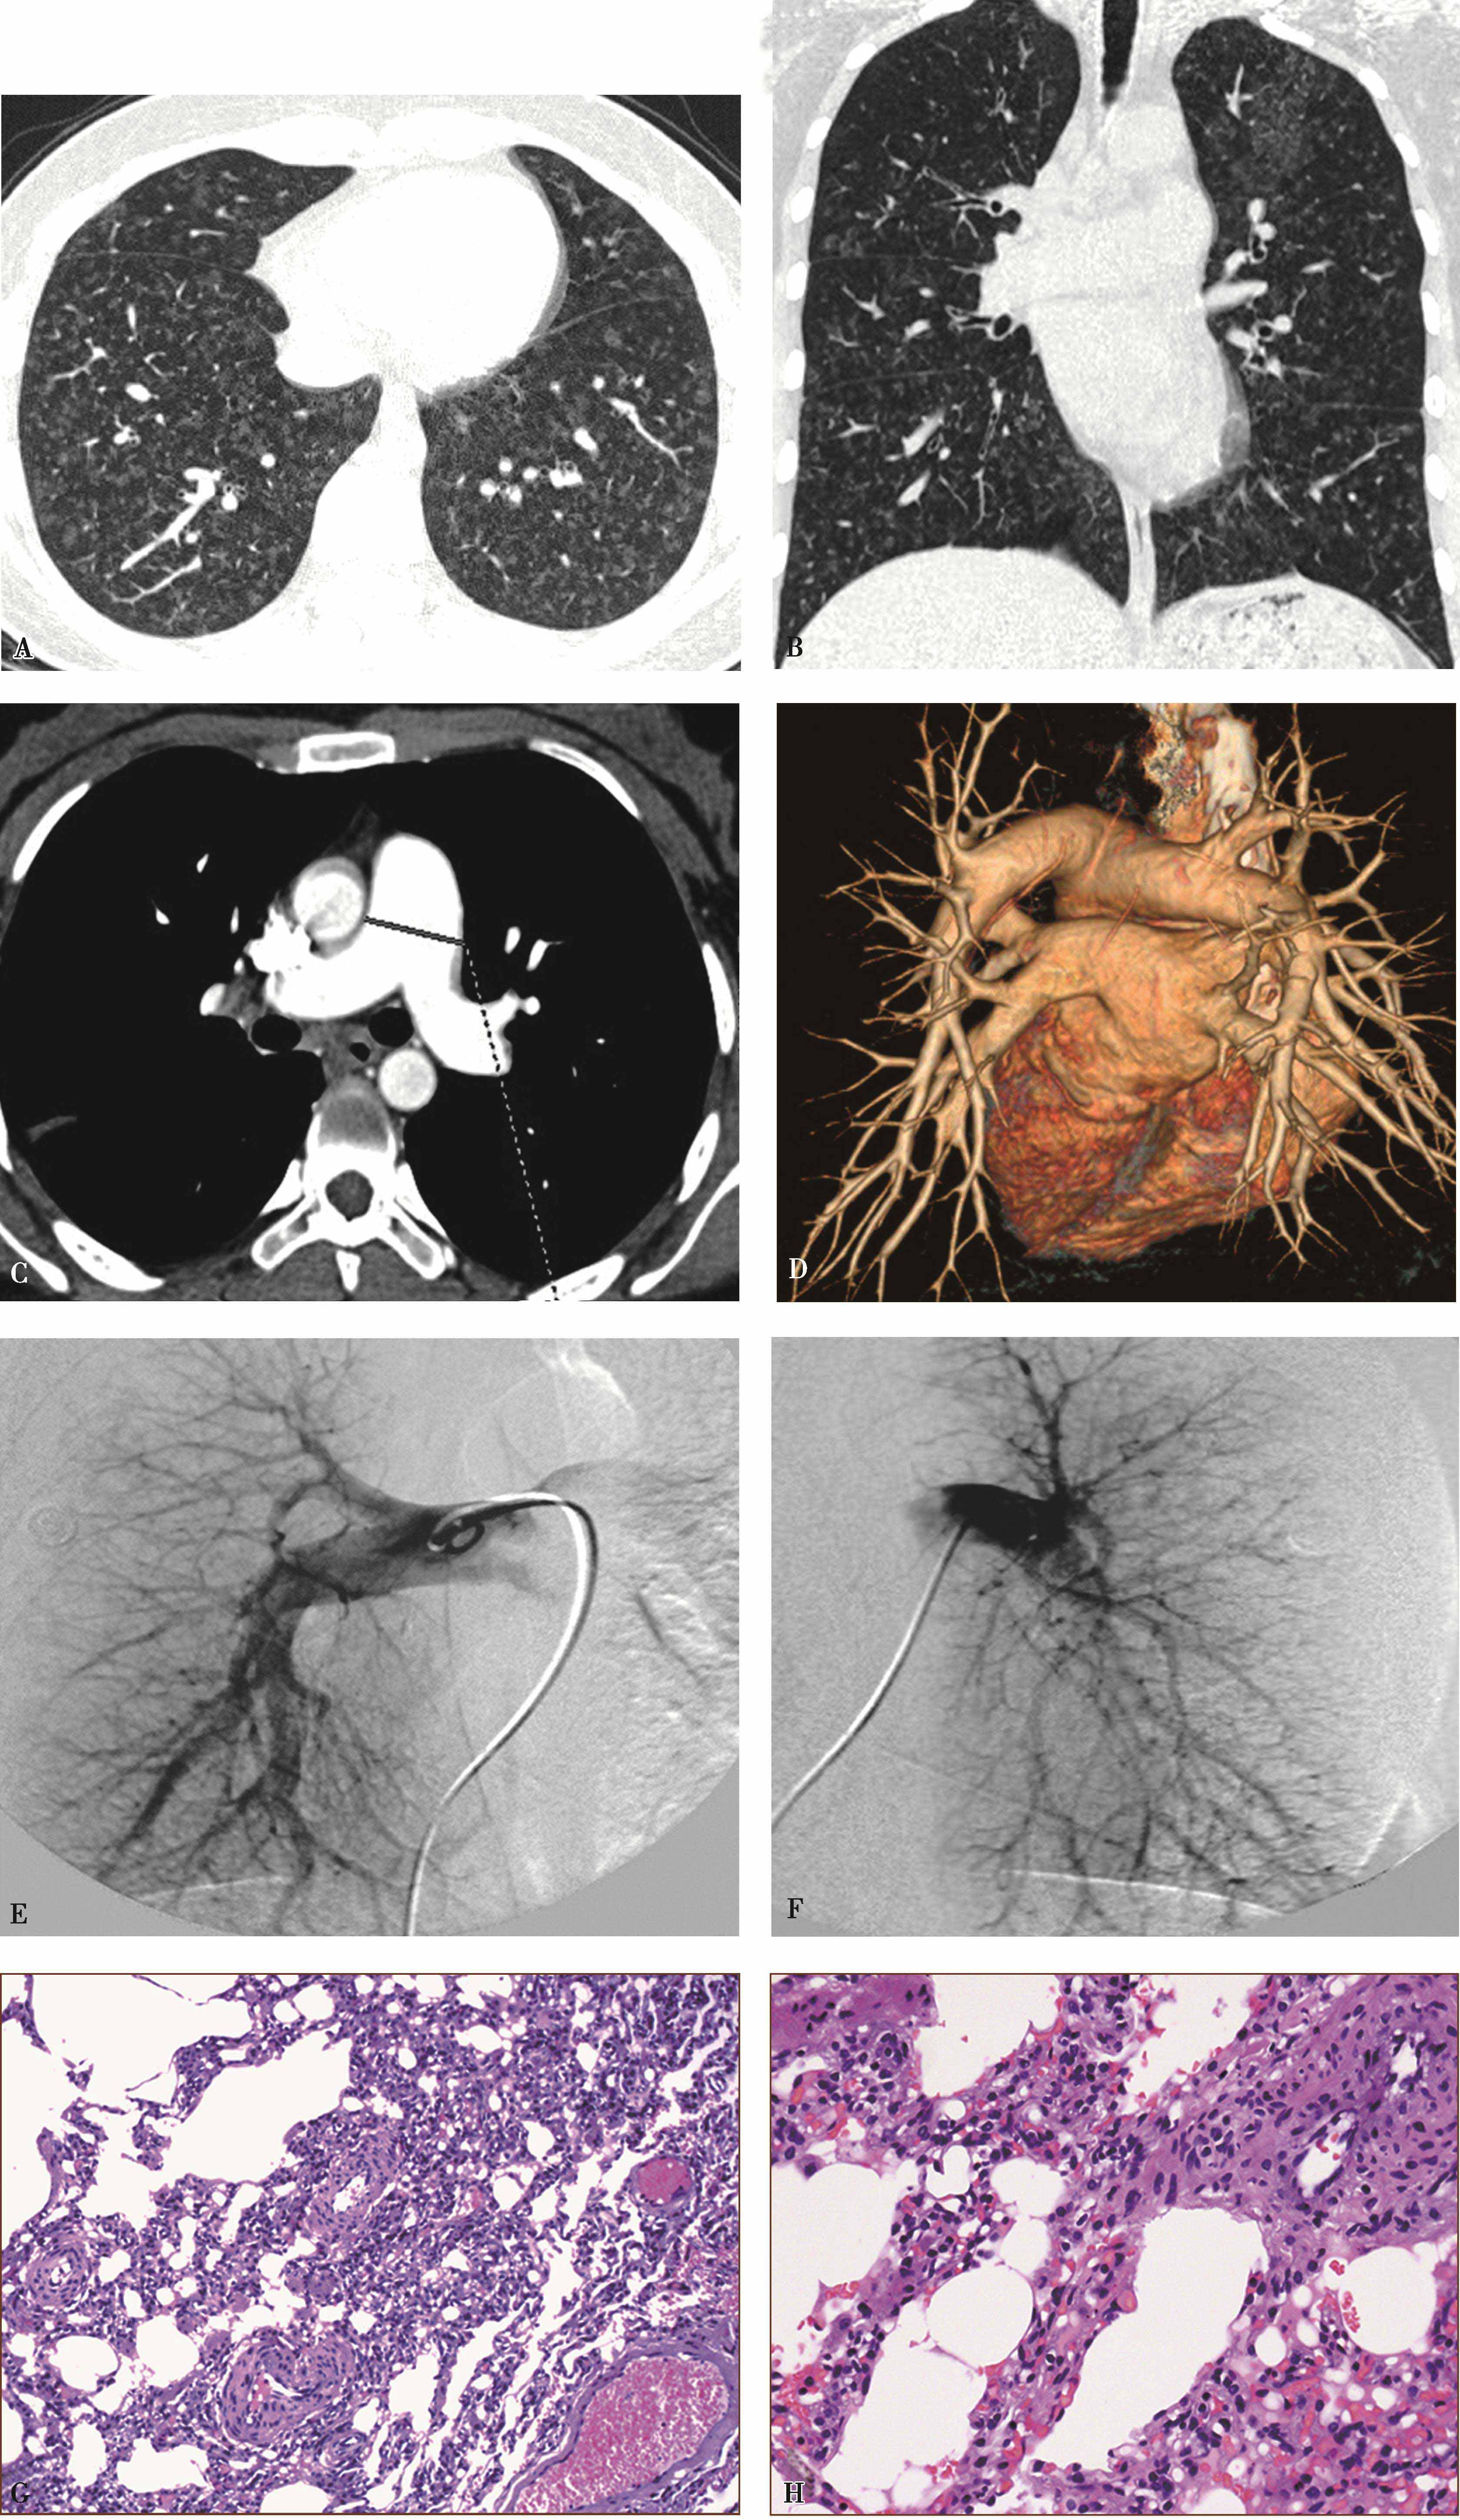

图8-11-2 女,19岁,进行性呼吸困难1年,病理诊断:毛细血管瘤病

A、B.横断图像及多层重组(冠状位)肺窗,显示磨玻璃结节影;C.CTPA示肺动脉增宽;D.VR肺动脉增宽,未见肺动脉栓塞及发育异常;EF.肺动脉造影未见异常;G-J.病理镜检(HE染色);G、H.肺泡间隔明显增厚,大量增殖的厚壁毛细血管;I、J.(CD34染色)毛细血管异常增殖。病理诊断:毛细血管瘤病